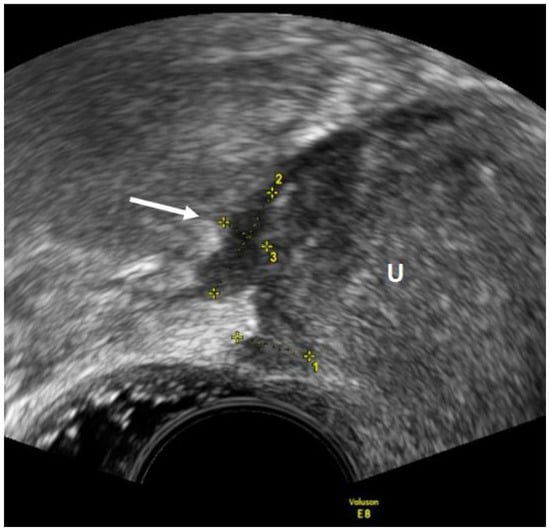

2.3. Deep Endometriosis

2.3.2. Posterior and Lateral Endometriosis

- Guerriero, S.; Condous, G.; van den Bosch, T.; Valentin, L.; Leone, F.P.G.; Van Schoubroeck, D.; Exacoustos, C.; Installé, A.J.F.; Martins, W.P.; Abrao, M.S.; et al. Systematic approach to sonographic evaluation of the pelvis in women with suspected endometriosis, including terms, definitions and measurements: A consensus opinion from the International Deep Endometriosis Analysis (IDEA) group. Ultrasound Obstet. Gynecol. 2016, 48, 318–332. [Google Scholar] [CrossRef] [PubMed]

- Leonardi, M.; Martins, W.P.; Espada, M.; Arianayagam, M.; Condous, G. Proposed technique to visualize and classify uterosacral ligament deep endometriosis with and without infiltration into parametrium or torus uterinus. Ultrasound Obstet. Gynecol. 2019, 55, 137–139. [Google Scholar] [CrossRef]

- Guerriero, S.; Alcázar, J.L.; Ajossa, S.; Pilloni, M.; Melis, G.B. Three-Dimensional Sonographic Characteristics of Deep Endometriosis. J. Ultrasound Med. 2009, 28, 1061–1066. [Google Scholar] [CrossRef]

- Guerriero, S.; Saba, L.; Ajossa, S.; Peddes, C.; Angiolucci, M.; Perniciano, M.; Melis, G.B.; Alcázar, J.L. Three-dimensional ultrasonography in the diagnosis of deep endometriosis. Hum. Reprod. 2014, 29, 1189–1198. [Google Scholar] [CrossRef]